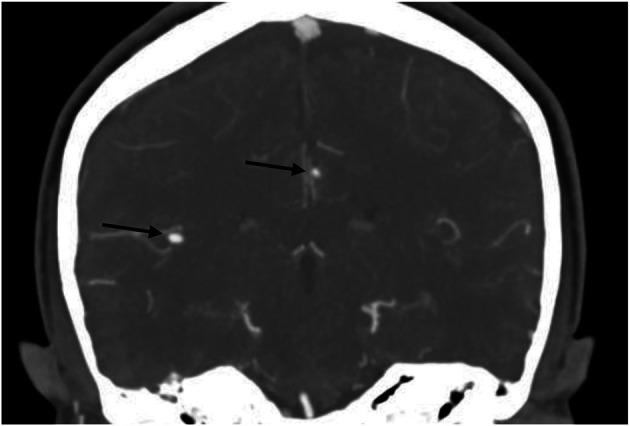

A 42-year-old woman with a known diagnosis of polyarteritis nodosa experienced several episodes of TIAs. Neuroimaging revealed 2 aneurysms in unusual locations. Her young age, ethnic origin, absent of cardiovascular risk factors, and skin involvement raised the suspicion of DADA2. Genetic testing confirmed the diagnosis, and a directed treatment with anti-TNF was initiated.

一名已知诊断为结节性多动脉炎的42岁女性经历了数次短暂性脑缺血发作。神经影像学检查发现2个位于不寻常位置的动脉瘤。她年轻、特定种族出身、无心血管危险因素以及皮肤受累情况引发了对DADA2的怀疑。基因检测确诊了该疾病,并开始了抗TNF定向治疗。